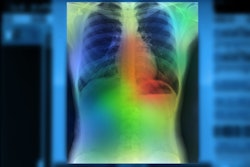

SmartCAD | COVID-19 uses Thirona's CAD4COVID-CT algorithm and Smart Reporting's COVID-19 reporting template to provide direct analysis of chest CT images and then transfers the results into a structured report.

The output includes a COVID-19 severity score on lung and lobar level, the percentage of abnormalities detected for each lobe and the lungs overall, and the percentage of lobar emphysema.